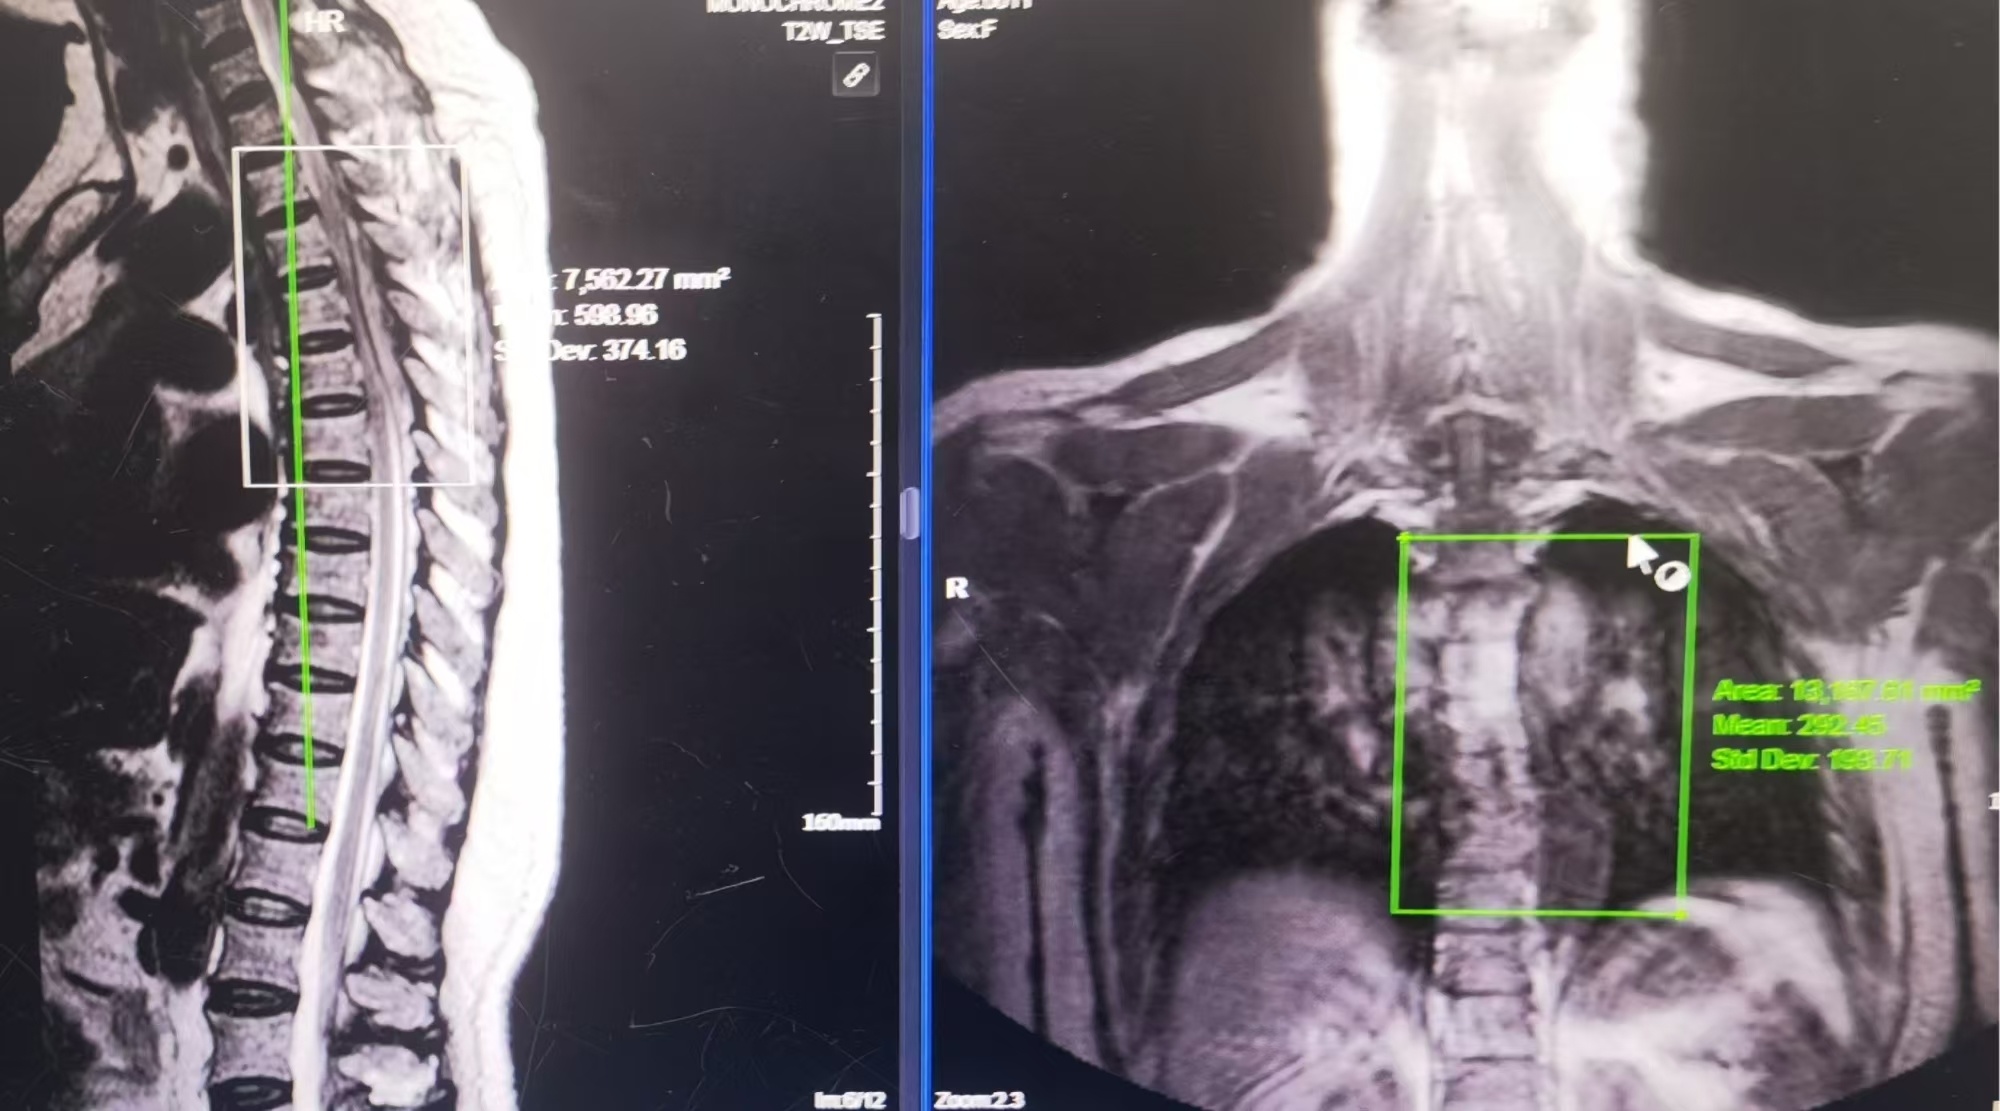

骨一區(qū)脊柱腫瘤陳志伸、歐清彬主任團隊進一步完善增強MRI、PET/CT等檢查,發(fā)現(xiàn)患者胸3-6多節(jié)段的椎管內(nèi)占位已引起脊髓功能障礙,如不盡快手術(shù)治療解除脊髓受壓,將導致神經(jīng)功能進一步惡化。

磁共振提示:胸3-6椎體水平椎管內(nèi)占位,椎管狹窄,脊髓受壓。